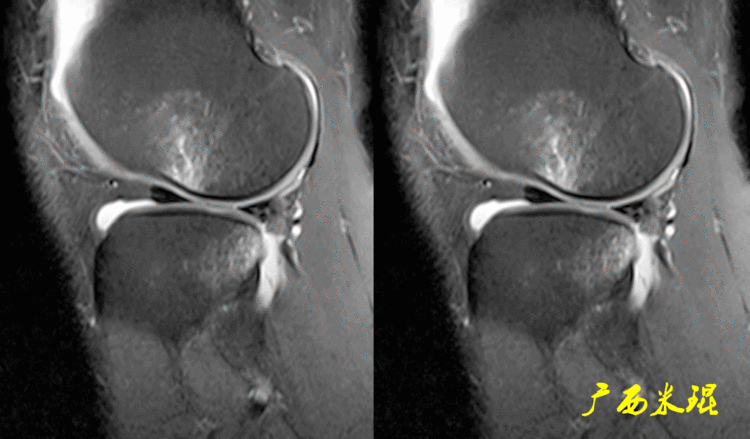

下面这张MR矢状位显示为类似双后交叉征,后交叉韧带前下方的低信号其实是正常的外侧半月板后角,半月板桶柄状撕裂多发生于内侧,绝大多数是前交叉韧带损伤的合并伤,此病人的前交叉韧带正常,通过其他截面的半月板阅片就能排除。

(2)隐窝隐窝是半月板后角与关节囊之间的正常凹陷,与体位等有关,可有可无,一般情况下积液越多隐窝越大,有上下之分,下面这张MR矢状位片见到的是上隐窝,紧贴半月板、光滑、不连通是其特点,也是鉴别要点。

下面这张MR矢状位片见到的是下隐窝,也紧贴半月板、光滑、不连通。